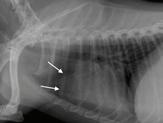

Se realizó una angio-TC de la cavidad torácica para caracterizar la masa mediastínica craneoventral. El estudio se realizó bajo anestesia general y con la paciente en decúbito esternal. Se realizaron series precontraste y post-contraste, inmediatamente y a los 3 minutos tras la administración de un contraste iodado hidrosoluble no iónico (iopromida 300 mg I/ml a una dosis de 600 mg I/kg intravenoso, administrado de forma manual) con cortes de 3 mm de grosor e intervalo 1,5 mm con algoritmo estándar (tejido blando) y pulmón. El estudio de TC se evaluó en ventana de tejido blando, hueso y pulmón, visualizándose en el área craneal al atrio derecho una estructura redon-

deada y bien definida (22UH) de medidas aproximadas 1,95 cm DV x 1,87 CrCd x 2,5 cm LL (Figs. 4 y 5). Tras la administración de contraste, esta estructura se llenó rápidamente de contraste de forma homogénea,

Figura 4. Imágenes de Tomografía Computarizada. Reconstruidas en plano sagital, simples (A) e inmediatamente tras la administración del contraste (B), en plano transversal, simples (C).

observándose una comunicación con el atrio derecho, midiendo el área de la comunicación 1,43 cm. El diagnóstico presuntivo fue de un aneurisma de la aurícula derecha.